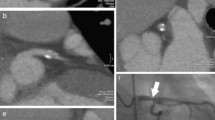

Non-calcified plaques were assessed quantitatively on an offline workstation (InSight, Neo Imagery, San Francisco, Calif.). The volumes of non-calcified plaques in the coronary artery wall were classified using thresholds of 0–130 HU. The outer border of the plaques was segmented manually, whereas the internal border between plaque area and contrast-enhanced vessel lumen was detected by the software and the plaque volume was calculated automatically (Fig. 1). The number, segmental location, and volumes of all non-calcified plaques, and the total non-calcified plaque volume burden per patient, were recorded.

Quantitative volumetry of non-calcified plaques. The quantitative volumetry was performed on an offline workstation (InSight, Neo Imagery, San Francisco, Calif.) The axial image at the height of the origin of the left coronary artery (left window) shows a large non-calcified plaque in the distal part of the left main coronary artery (arrow). Volumetry was conducted semi-quantitatively, segmenting the soft plaque borders by hand, whereas the software measured plaque volume automatically according to predefined thresholds (right window, see ellipsis for results)

In our cohort of 179 patients, combining a non-contrast-enhanced calcium screening with a contrast-enhanced coronary angiography, 7 patients (4%) were identified with non-calcified plaques only, i.e., no calcifications were found in the calcium screening test. In these 7 patients, catheter angiography showed minor (stenoses <50%, 4 patients) or major (stenoses >75%, 2 patients) vessel lumen changes, but 1 patient had normal vessel lumen in catheter angiography and the presence of coronary atherosclerosis would have been missed by the gold-standard modality (Fig. 4). This specific subgroup of 7 patients showed an overall higher risk factor profile, with a higher percentage of nicotine abuse (83%), obesity (67%), hypertension (67%), and diabetes (50%; all 179 patients: 46, 28, 55, and 21%, respectively). Also, a lower mean age (55±10 vs 61±12 years) and a lower number of male patients (43 vs 68%) was characteristic for this cohort. Due to the small patient number in this subgroup, these differences were not statistically significant. Still, the non-contrast-enhanced calcium screening examination would have missed CAD in these patients, only after performing a CT angiography the correct diagnosis was made. Further characterization of such patients at risk for non-calcified plaques is essential for correct indication of contrast-enhanced MDCT angiography.

Example of a correct diagnosis made by multidetector-row computed tomography (MDCT) angiography. A 38-year-old man with a high cardiovascular risk factor profile and atypical angina underwent a calcium screening test, an MDCT coronary angiography, and conventional cardiac catheterization. The calcium screening examination was negative. No calcifications were found in the A coronary arteries (arrow), but after administration of contrast, a non-calcified plaque was detected in the B left main coronary artery (arrow). C Catheter angiography did not show any significant stenoses in this area, most probably due to "positive remodeling" effects (arrow)